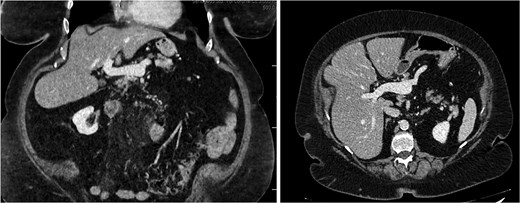

A 45-year-old male presenting with a 10-day history of isolated right lower quadrant (RLQ) abdominal pain. His history included deep vein thrombosis, coronary artery disease with prior STEMI, left anterior descending artery stenting in 2014, and ongoing antiplatelet therapy with aspirin. Upon admission, RLG tenderness was noted. Laboratory revealed leucocytosis (WBC 16 G/L) and elevated CRP (70 mg/L). E-CT revealed superior mesenteric and portal systems thrombosis with ischemia of a small bowel loop in the RLQ, characterized by absent bowel wall enhancement and free fluid (Fig. 4). Besides these findings, he was managed conservatively with a UFH bolus of 5000 U/l, followed by a continuous infusion of 36 000 U/l over 24 h (target INR 0. 35–0. 7), Ceftriaxone and Metronidazole, bowel rest, and ICU monitoring for 48 h. Clinical and biological improvement was rapid. E-CT on the second day showed no signs of perforation (Fig. 5). He was discharged after 7 days on LMWH (enoxaparin sodium 90 mg every 12 h). Twenty days later, he re-presented with acute RLQ pain and localized peritonism. E-CT revealed a covered perforation of the previously ischemic small bowel loop (Fig. 6). A segmental bowel resection with primary anastomosis was performed by laparotomy (Fig. 7). The postoperative course was uneventful, and he was discharged on postoperative day 4 with sodium enoxaparin 90 mg/12 h.

E-CT in the second patient at admission. White arrows showing porto-mesenteric thrombosis. Dashed arrows indicate a portion of small bowel loop ischemia in the right lower quadrant characterized by the absence of bowel wall enhancement and free fluid.